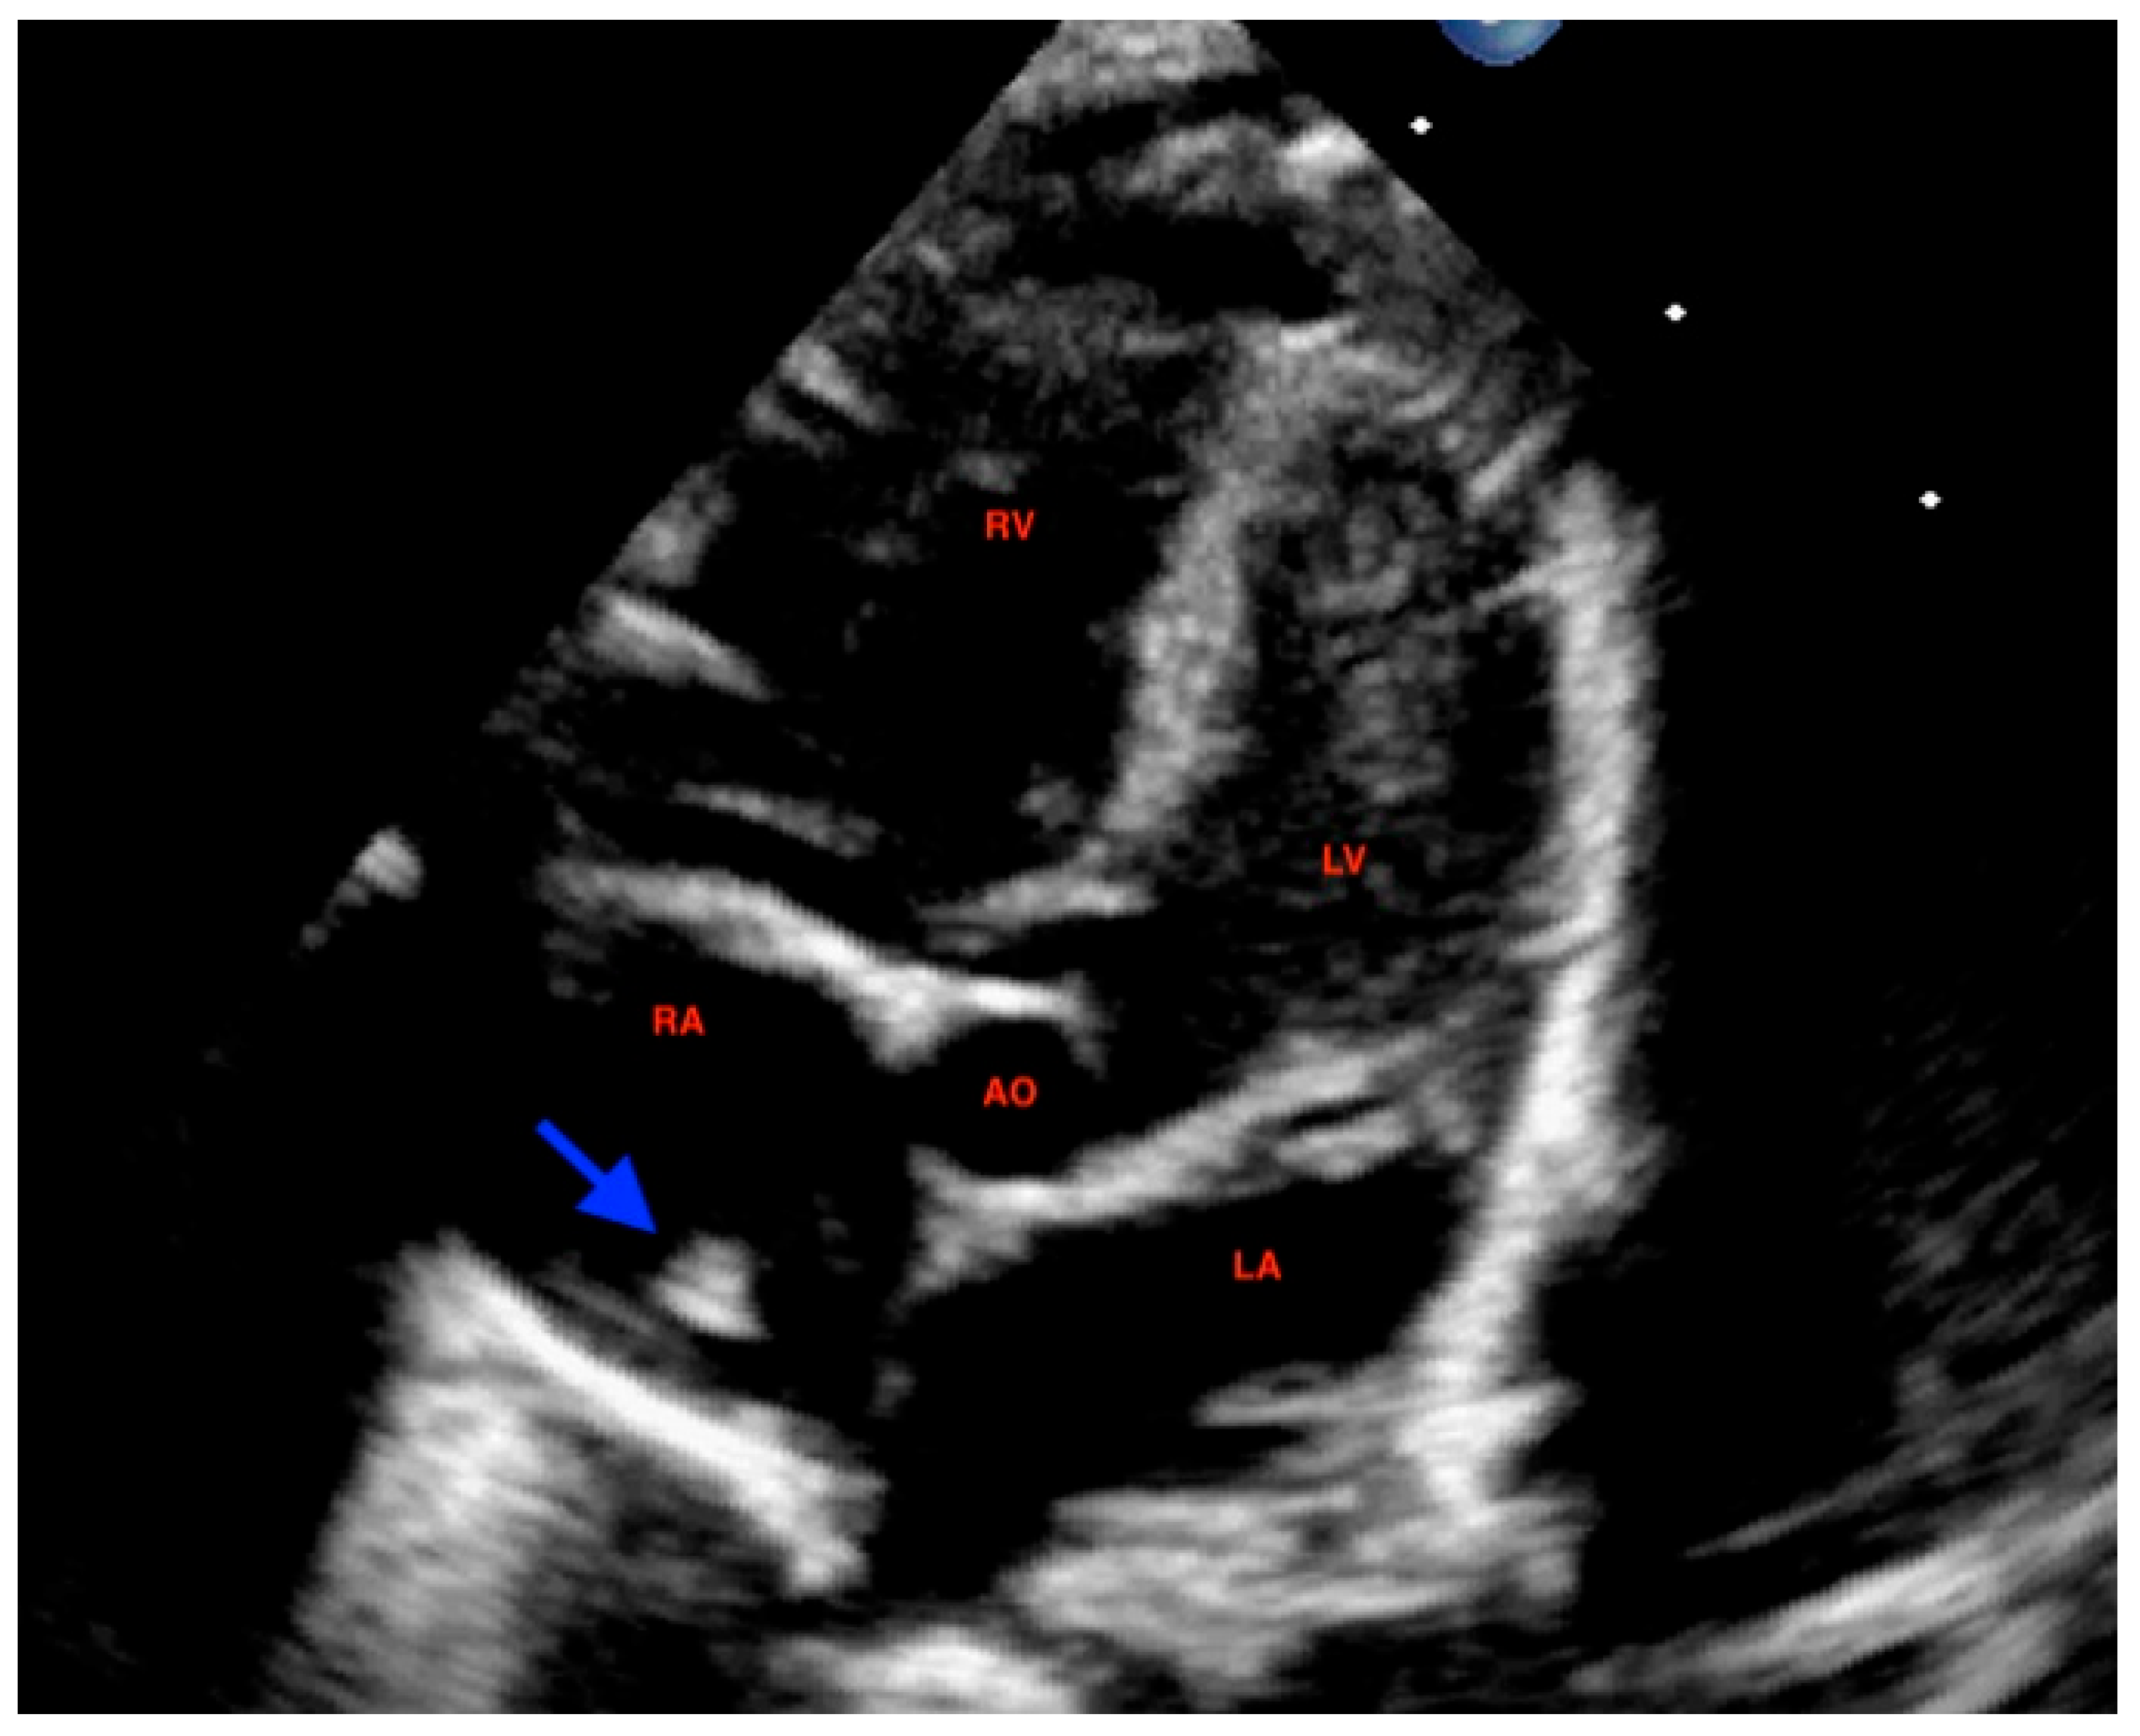

Figure 1. 4-Chamber view at 32 + 4 week scan, demonstrating untypical hyperechogenic mass (3.7 mm × 2.9 mm) (arrow) being diagnosed in the later course as a prominent crista terminalis. 1, 2: interatrial septum.

At 32 weeks, a third-trimester US revealed a hyperechoic, well-defined, round mass in the fetal right atrium measuring 3.7 × 2.9 mm. The mass extended from the SVC to the IVC, along the posterior and lateral atrial wall. Cardiac blood flow remained normal, and no associated structural cardiac anomalies were identified.

Additionally, a thin membranous structure was observed traversing the right atrium and inserting at the superior aspect of the interatrial septum. This structure did not impede intra-atrial flow. Doppler evaluation of the ductus venosus demonstrated normal waveforms The differential diagnosis included HCT, atrial myxoma, rhabdomyoma (less likely), and intra-atrial thrombus. However, serial US executed during the remainder of the pregnancy displayed no changes in the size or characteristics of the mass (Figure 1 and Figure 2). Therefore, HCT was the favored diagnosis and no prenatal or postnatal MRI was planned. The US scans in pregnancy were defined in accordance with the most up-to-date evidence as there are no documented prenatal consequences of HCT [1]. Although there are no established guidelines for HCT, the American Heart Association and the American Society of Echocardiography (AHA/ASE) recommend repeated imaging in 2–4 weeks of the initial examination is incomplete or a progressive lesion is suspected, and the management must be individualized to the specific case [10].

At 72 h of life, postnatal transthoracic echocardiography demonstrated a persistent hyperechoic mass in the right atrium, not grown and not modified compared to previous scans, and interpreted as HCT. There was no evidence of right atrial inflow obstruction, and no mass growth was observed (Figure 3).